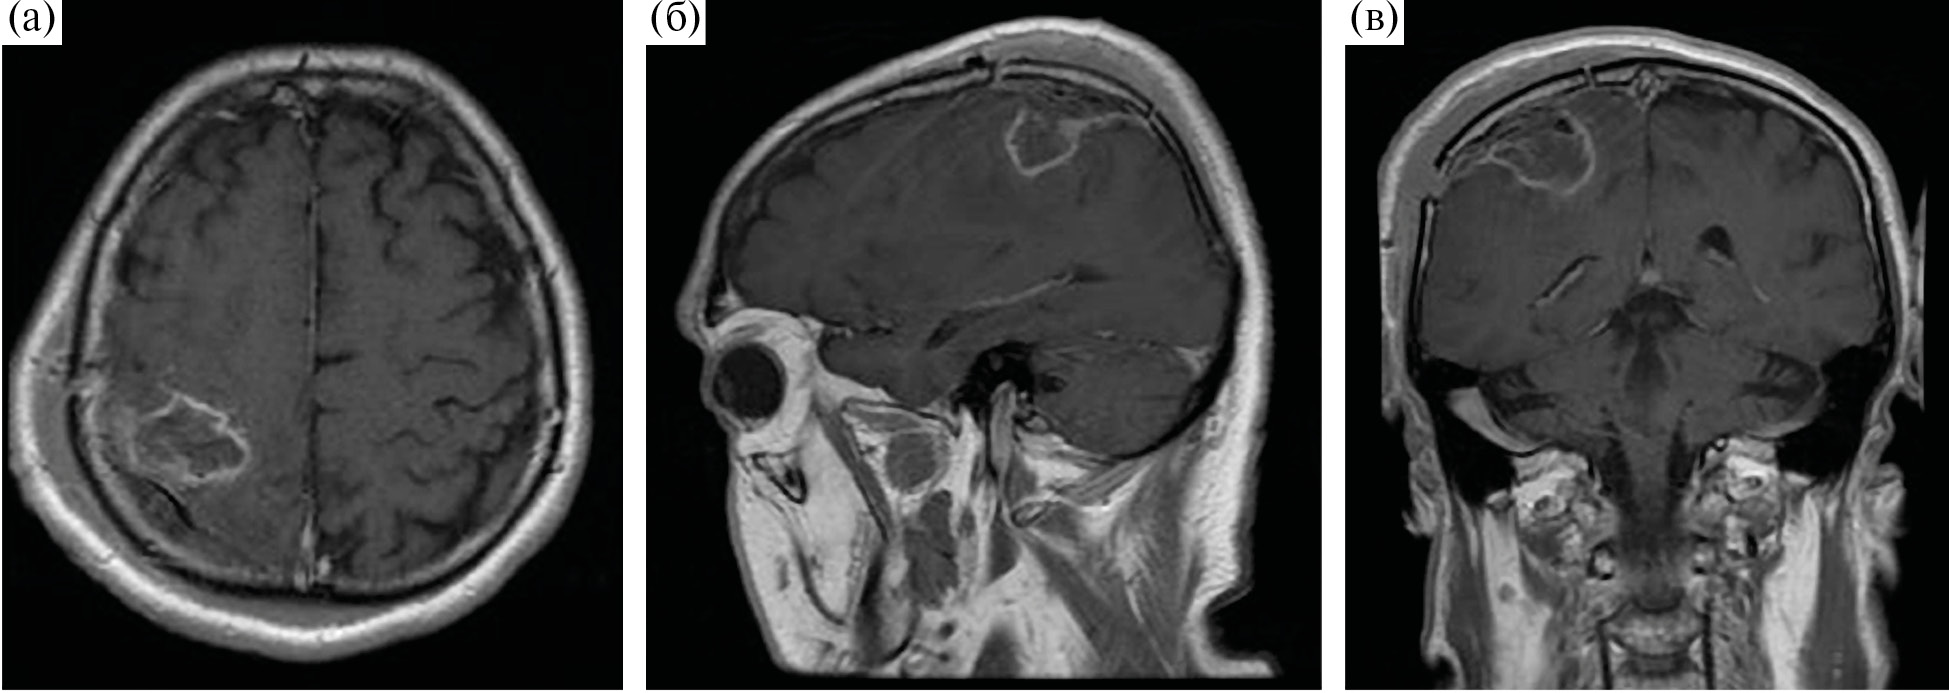

Аласенс (препарат 5-аминолевуленовой кислоты) вводился перорально за 2 ч до разреза ТМО из расчета 20 мг/кг. Из исследования были исключены 12 пациентов, у которых не отмечалось визуальной флуоресценции во время операции. Всем пациентам была проведена оценка мышечной силы до операции, на первые и седьмые сутки после хирургического лечения, выполнена предоперационная МРТ (Т1, Т2, Т2-FLAIR, DWI, T1+C, DTI) с определением расстояния от опухоли до КСТ и типа взаимоотношения между трактом и новообразованием. Было показано, что из 108 пациентов у 21 (19.4%) наблюдался интактный КСТ, у 43 (39.8%) – смещенный, у 34 (31.5%) – смещенный и инфильтрированный, у 8 (7.4%) – инфильтрированный, и только в одном наблюдении опухоль располагалась в структуре тракта, расщепляя его (рис. 1).

Рис. 1. (а) – пример интактного КСТ по данным ДТ-трактографии у пациента с глиобластомой. Тракты симметрично расположены и не отличаются значимо по объему. (б) – пример смещенного КСТ, по данным ДТ-трактографии у пациента с глиобластомой. Тракты не вовлечены в опухоль, однако положение их отличается. (в) – пример инфильрированного КСТ, по данным ДТ-трактографии у пациента с глиомой Grade IV. Несмотря на вовлечение КСТ в опухоль, по данным Т2-FLAIR отмечается правильное, симметричное положение тракта. (г) – пример смещенного и инфильтрированного КСТ, по данным ДТ-трактографии у пациента с глиобластомой. Тракты расположены асимметрично и вовлечены в зону отека-инфильтрации. (д) – пример расщепленного тракта у пациента с анапластической астроцитомой. Опухоль располагается внутри КСТ, расщепляя его волокна.

Fig. 1. Different types of relationship between the corticospinal tract and the tumor according to MR-tractography (intact, displaced, infiltrated, displaced and infiltrated, split).